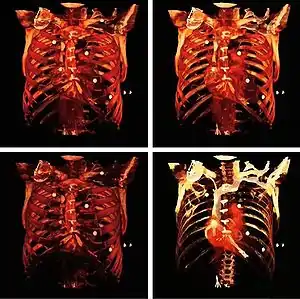

مقطع نگاری کامپیوتری (CT)

این روش تلفیق استفاده از توموگرافی معمولی(مقطع نگاری) با پردازشهای کامپیوتری میباشد. در این روش نیز از اشعه X استفاده میشود. البته دوز مورد استفاده در این روش بسیار بالاست و تفاوتهای ساختاری ای مثل استفاده از حرکت لامپ تولیدکننده اشعه X یا حرکت آشکارساز، همچنین گاهی آشکار سازهای حلقوی دور بیمار و ...، با رادیو گرافی معمولی، دارد.

ولی تصاویری از سطح مقطعهای مختلف، در عمق دلخواه از اعضای بدن را، میدهد. در رادیوگرافی معمولی اطلاعات مربوط به عمق از دست میرفت. از طرفی نمیتوانست بین نسوج نرم تمایز ایجاد کند. طبعاً اطلاعات کمی مربوط به چگالی بافتها را نیز، در اختیارمان نمیگذاشت . در مقطع نگاری معمولی مشکل اول، یعنی تصویربرداری از یک مقطع دلخواه حل شد، ولی مقطع نگاری کامپیوتری دو مشکل دیگر رادیوگرافی معمولی را نیز حل کرد. یعنی حساسیت مورد نیاز برای تمایز بین نسوج نرم را دارا میباشد، همچنین اطلاعات کمی دربارهٔ میزان تضعیف (ناشی از عبور اشعه از نسوج)را نیز میدهد. البته در این روش قدرت تفکیک بهبود نیافته و تنها بخشهای ناخواسته ، تارتر میشوند.

در حال حاضر سالیانه بیشتر از ۶۲ میلیون از این روش در آمریکا،استفاده میکنند و بر اساس تخمین یکی از نشریههای معتبر آمریکایی ۲٪ سرطان ها(نوع بدخیم) ناشی از دوز بالای استفاده شده در این روش است. تلفیق دو روش PET و CT که تحت عنوان PET/CT شناخته شدهاست ، روش جدیدی ست که در آن اطلاعات مربوط به آناتومی (حاصل از CT) با اطلاعات متابولیکی که مربوط به عملکرد و اجزا میباشند (آنچه که PETدر اختیارمان میگذارد) تلفیق شده و روشی مطلوب بخصوص در مطالعه تومورها میباشد. نکته حائز اهمیت، عدم ضرورت استفاده از دوز بالای CT در این روش است. این روش ۸۵٪ در مطالعه تومورها (تشخیص سلولهای بدخیم از خوش خیم، مشاهده دقیق روند پیشروی سلولهای سرطانی و بررسی پاسخ به درمان و رادیوتراپی)، ۱۰٪ در نورولوژی ،۵٪ در مطالعات قلب، استفاده میشود.